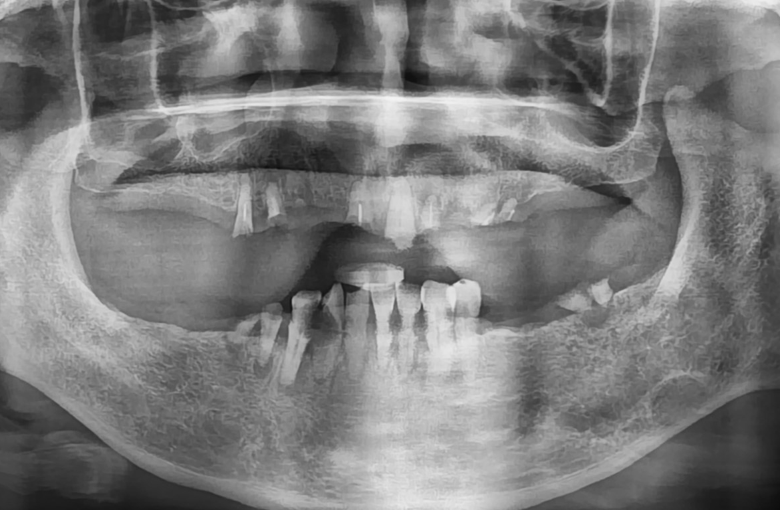

80대 환자분으로, 전체틀니를 사용 중이셨는데 아래 틀니가 자주 잇몸에서 떨어져 불편함을 호소하셨습니다.

전체 틀니를 다시 제작하는 방법도 있지만, 최소한의 임플란트로 틀니를 잡아주는 치료를 결정하였습니다. 고령인 점 고려하여 무리가 가지 않게 무절개/최소절개로 4개의 임플란트를 식립하고 임플란트 똑딱이 장치를 이용하여 임플란트와 기존 쓰시던 틀니를 연결하였습니다.

60대 환자분으로, 최소 비용으로 전체 치아를 만들고 싶다고 하셨습니다. 전체 틀니를 하는 경우가 최소비용으로 치료할 수 있는 방법이나 아래쪽 틀니를 아무리 잘 만든다 하여도 항상 움직이는 혀와 틀니를 받혀주는 잇몸뼈가 부족해서 사용할 때마다 불편감이 클 것으로 예상되었습니다.

따라서 아래쪽 앞니 쪽에 틀니를 잡아줄 수 있는 임플란트 두 개를 식립하여 두 개의 임플란트들을 연결하여 아래 앞니 6개를 만들어 드린 후, 어금니쪽은 부분 틀니로 보강하는 치료 방법을 선택하였습니다. 위쪽은 전체 틀니를 만들어 드렸습니다.